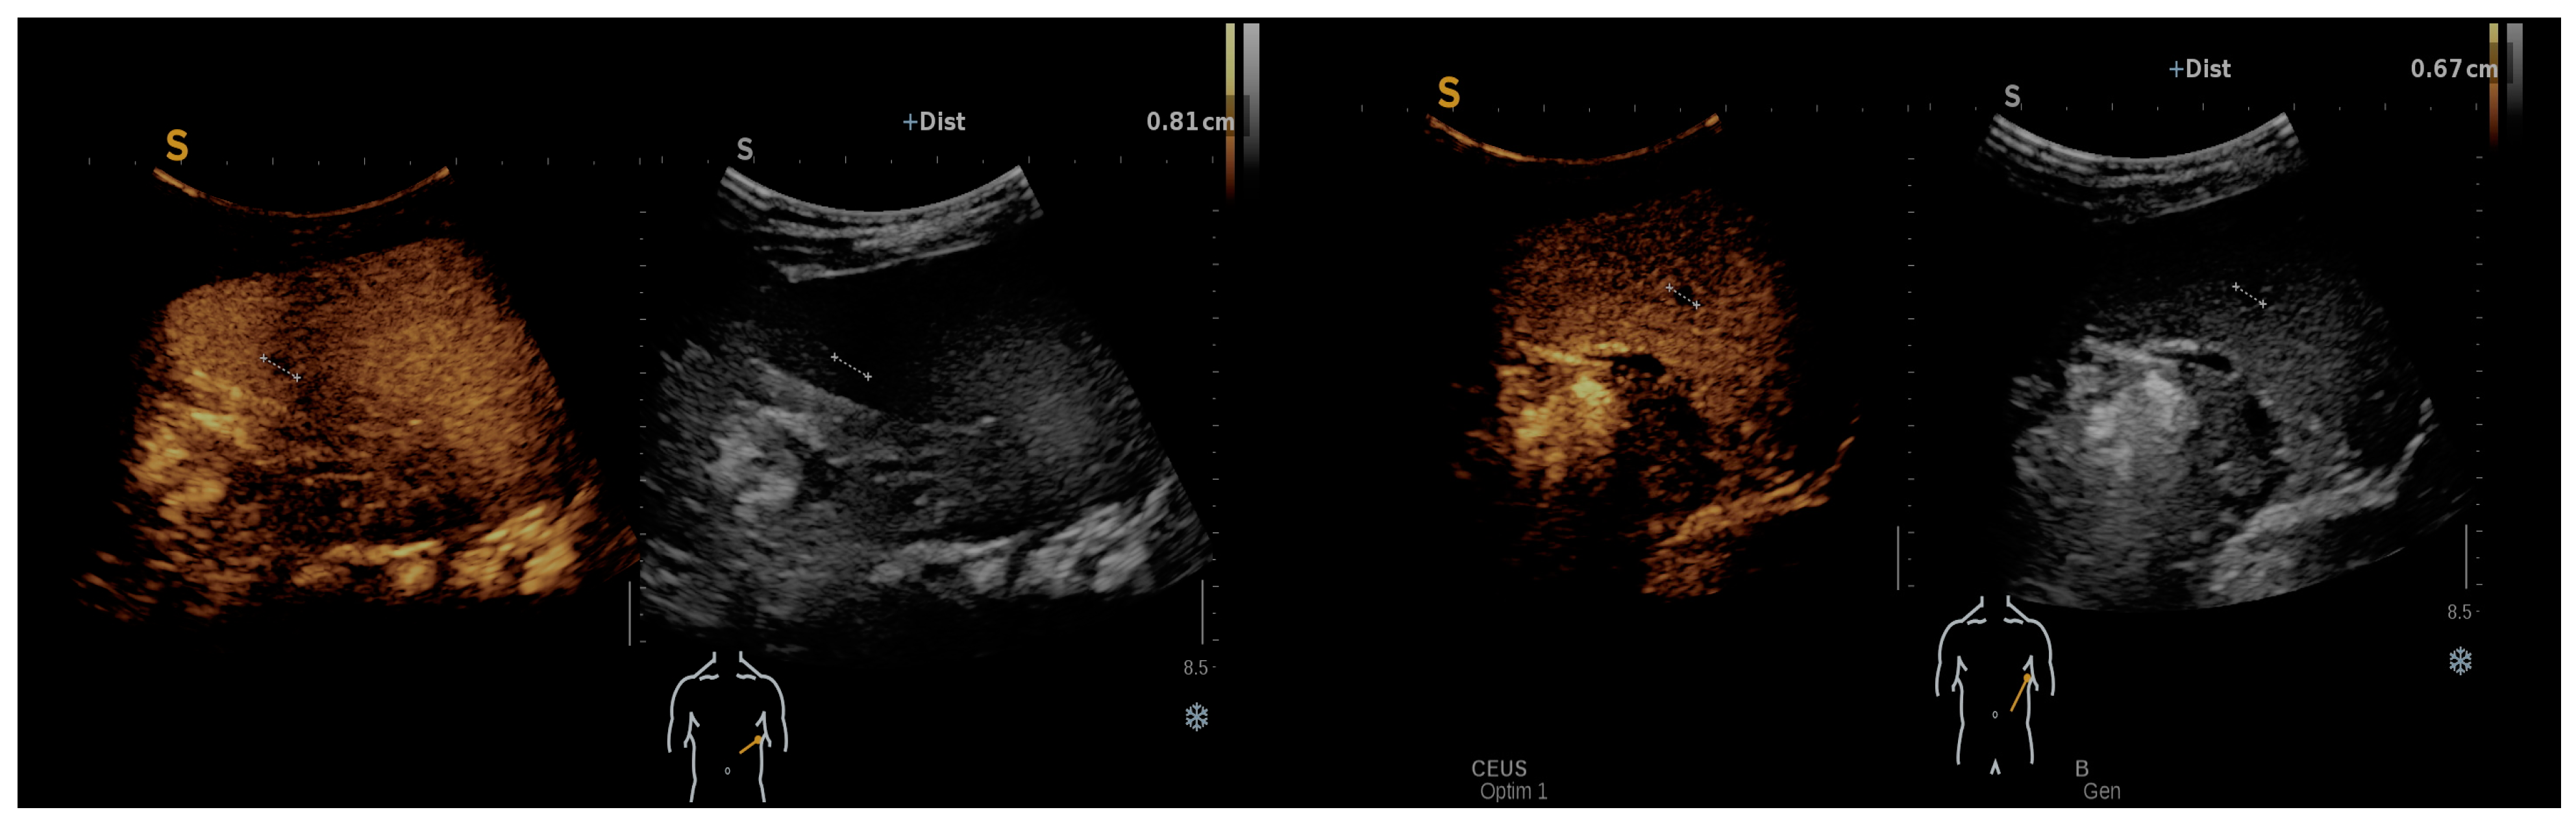

In the follow-up assessment of some patients using contrast-enhanced ultrasound (CEUS), significant findings were observed that provided deeper insights into the progression and response to treatment of Bartonella infections. One-month post-treatment, CEUS was performed, revealing a spleen of 9.6 cm. During the arterial phase of imaging, the spleen demonstrated uniform enhancement, characterized by a unique geographic pattern. Notably, this pattern included two distinct non-enhanced regions, one approximately 8 mm in size located at the lower pole and another measuring roughly 7–8 mm near the hilum. These CEUS findings, as illustrated in Figure 3, suggested the presence of splenic abscesses potentially in a state of healing, contrasting with earlier ultrasound results. The homogeneous enhancement across the spleen, punctuated by these well-defined round/oval non-enhancing areas, raised the possibility of a recuperative process underway within the organ, indicating a positive response to the administered treatment.

Figure 3. CEUS: homogeneous enhancement revealing two well-defined splenic round/oval non-enhancing areas.